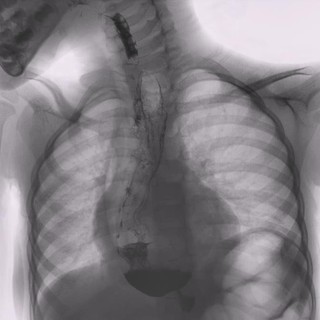

A Torino il 7° Congresso Nazionale della Società Italiana per lo Studio delle Malattie dell’Esofago